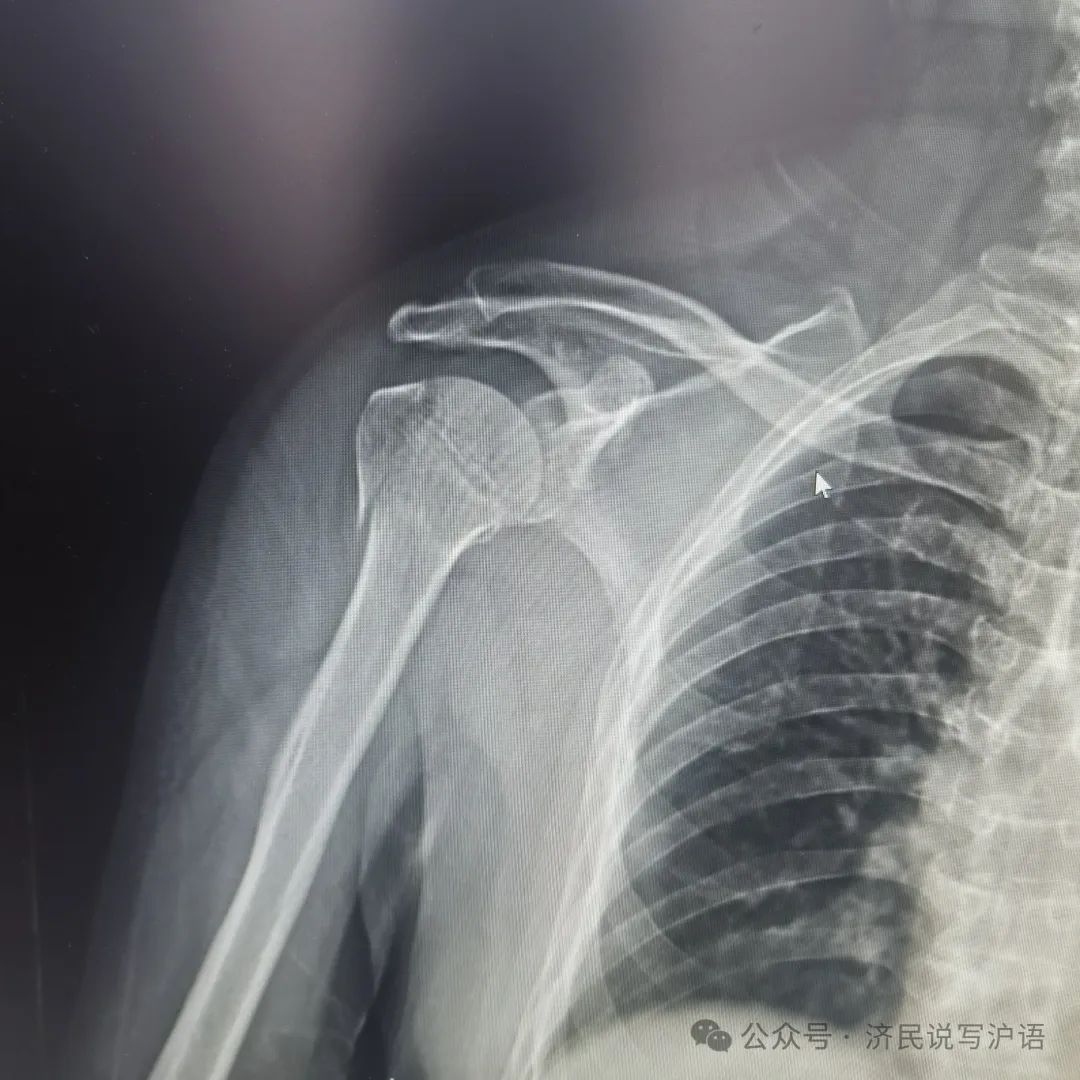

拍片确诊骨折后,医生说要手术,要装钢板,手术时要全麻,并当即给我开出住院通知单。我问可否保守治疗,医生说可以,用吊带吊着手臂,让它慢慢长。但恢复慢,且手臂功可能能会受影响。我想,既然可保守治疗那就保守治疗吧,不但可少受苦,也避免全麻造成对脑子的损伤。至于恢复慢些则无所谓。我已76岁了,垂垂老矣,功能受些影响也无碍。于是毫不犹豫决定保守治疗,立即用绷带把右臂吊了起来。实践证明我的决断是正确的。要是真动了手术,吃苦不说,后果还真难料。

我堂叔是著名医学院的博导,得知我骨折,即请他学生、某大医院骨科主任帮我看片。他支持保守治疗。有专家指导,我放心不少。